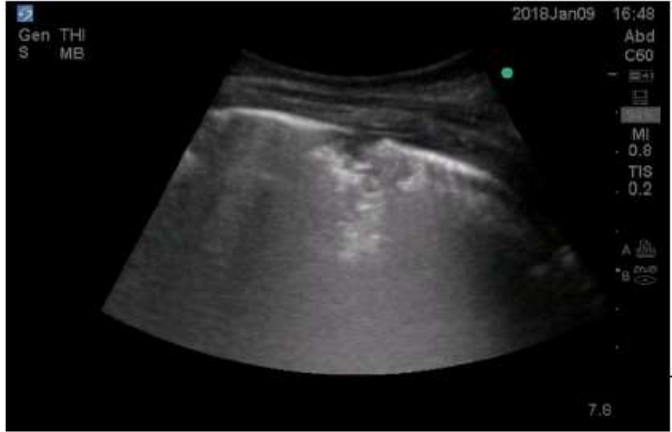

Consolidation in lung ultrasound may be identified as tissue-like echogenicity. Small consolidations (some authors refer to it as subpleural consolidations [6], however some believe the name to be inappropriate [14]) are echo poor regions approximately 0.5 cm in diameter with the presence of shred sign- the irregular border in between the consolidated and aerated lung tissue [15]. Air bronchograms are hyperechoic artifacts within the consolidation and are said to be dynamic if they move centrifugally more than 1 mm during inspiration [16] (Figure 1and 2).

Figure 2: Small consolidation with shred sign.